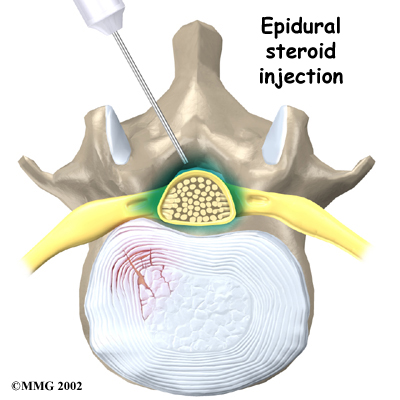

Some patients who continue to have symptoms are given an (ESI). Steroids are powerful anti-inflammatories. In an ESI, medication is injected into the space around the lumbar spinal nerves where they branch off of the spinal cord. This area is called the epidural space. Some doctors inject only a steroid. Most doctors, however, combine a steroid with a long-lasting numbing medication. Generally, an ESI is given only when other treatments aren't working. But ESIs are not always successful in relieving pain. If they do work, they often provide only temporary relief.